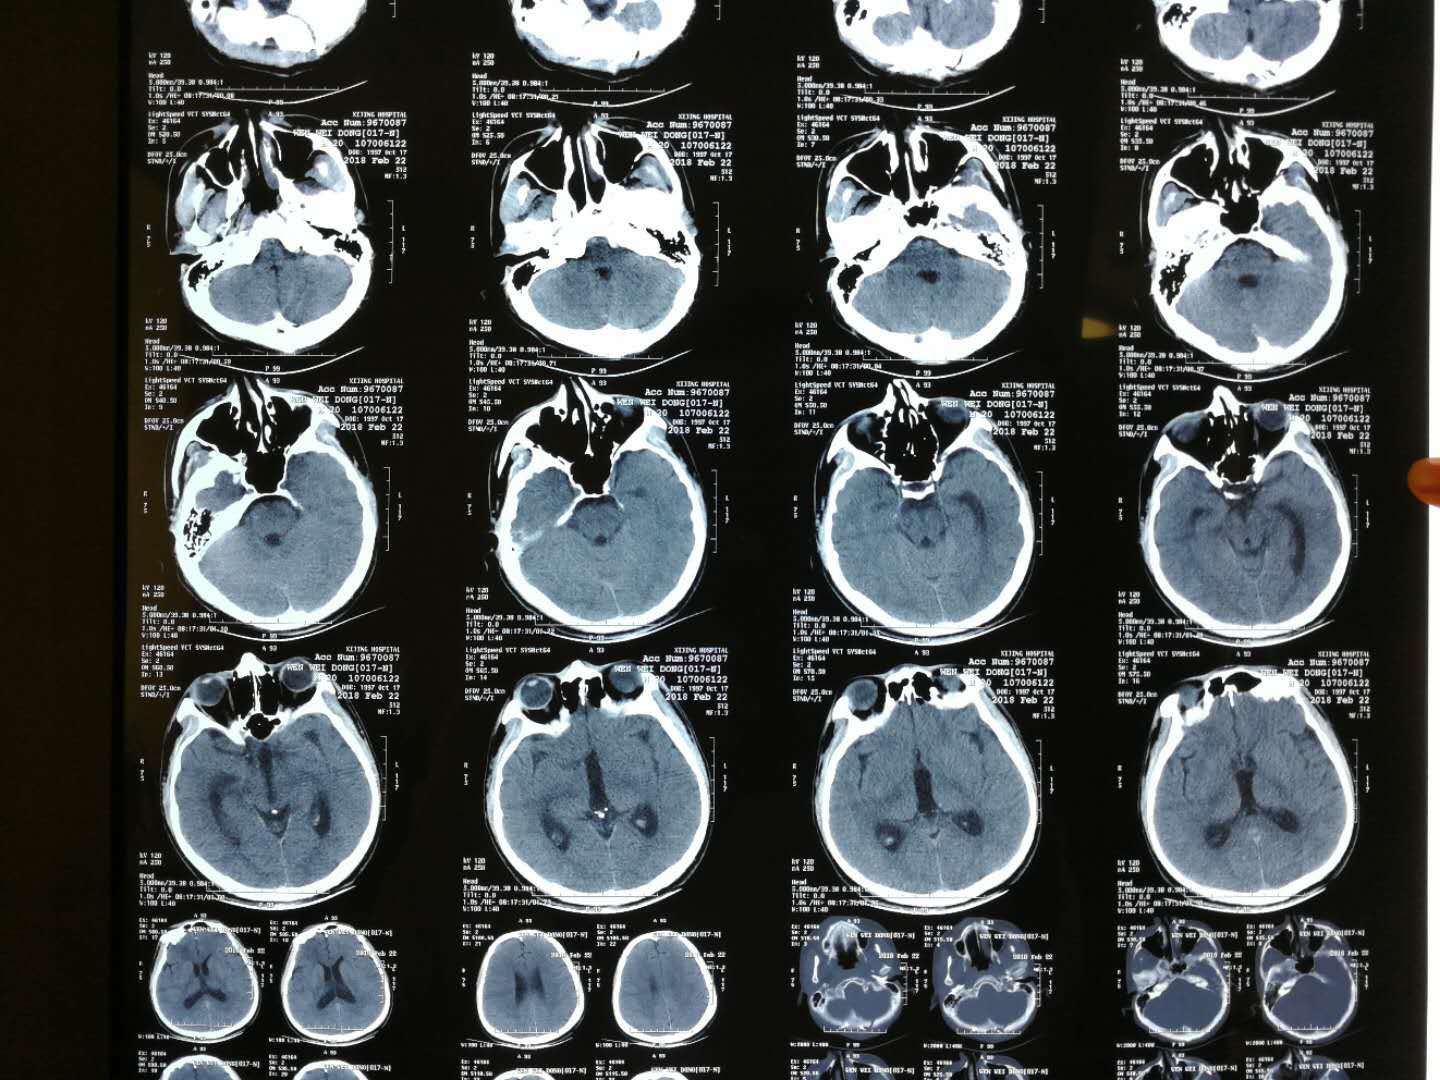

【读片】一例四脑室肿瘤 [病例帖]

第四脑室肿瘤-ct-病理已公布